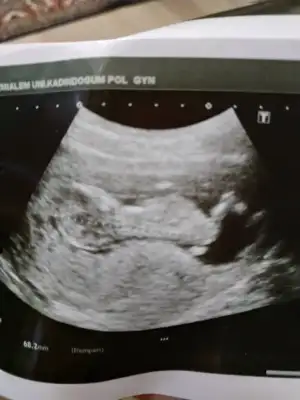

Kız sanki başka usg varmı 11+ yada 12+ olmalı100 de 100 kızım diye bağırıyor dimi kizlar:) yanılıyor muyum?11+1

Çelişkide mi kaldınız? Sizin yorumunuz benim için önemli.. Yok başka fotosu bi bu var. Zaten daha12 haftalık olmadiKız sanki başka usg varmı 11+ yada 12+ olmalı

Şimdilik kız diyorumÇelişkide mi kaldınız? Sizin yorumunuz benim için önemli.. Yok başka fotosu bi bu var. Zaten daha12 haftalık olmadi

Altta ki erkek sankiTeşekkür ederim . İkisi de mi![]()

Sağlıkla gelsin biri kız bi erkek diyorum